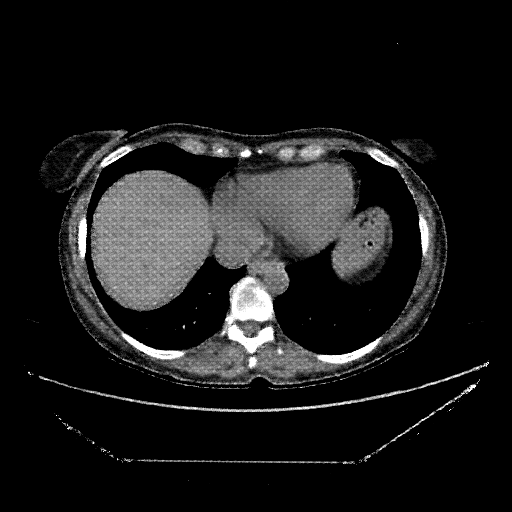

Generated VENOUS CT scan (A→B translation)

No window - Raw intensity values

Lung window (WL -600, WW 1500 β†’ Low βˆ’1350, High +150)

Mediastinum window (WL 40, WW 400 β†’ Low βˆ’160, High +240)